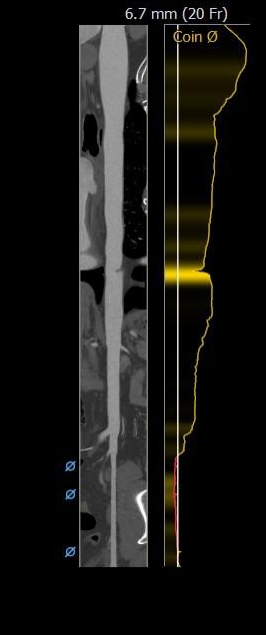

主动脉根部评估

外周分析

• 根据根部及瓣上分析,该患者钙化不重,瓣口较大,采取不预扩,直接植入TaurusElite AV31型号瓣膜策略,瓣膜释放后观察形态,必要时采用25mm球囊进行后扩;